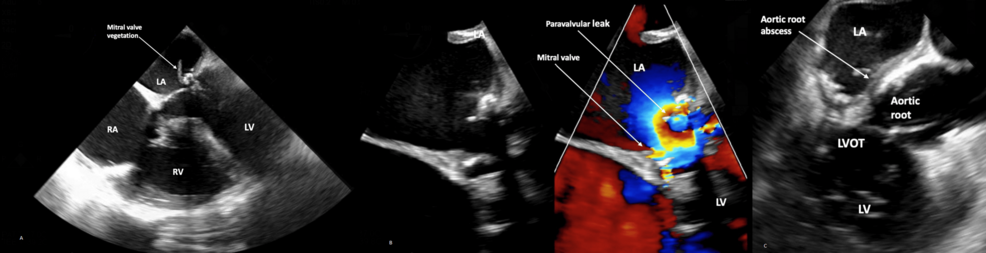

2. Echocardiographic Findings: Transesophageal echocardiography (TEE) reveals mitral valve vegetations and evidence of an aortic root abscess – a localized collection of pus surrounding the aorta.

Transesophageal Echocardiography (TEE): Superior to transthoracic echocardiography (TTE) for visualizing the aortic root and detecting small abscesses.